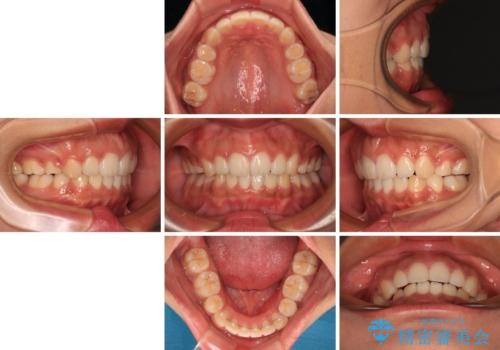

舌の突出癖により上下前歯は非接触であり、非常に前方に飛び出している状態でした。

舌のトレーニングをしっかりと行っていただき、口の閉じやすい歯並びに仕上げることができました。

口が閉じられない 抜歯矯正で横顔の印象が劇的に変化